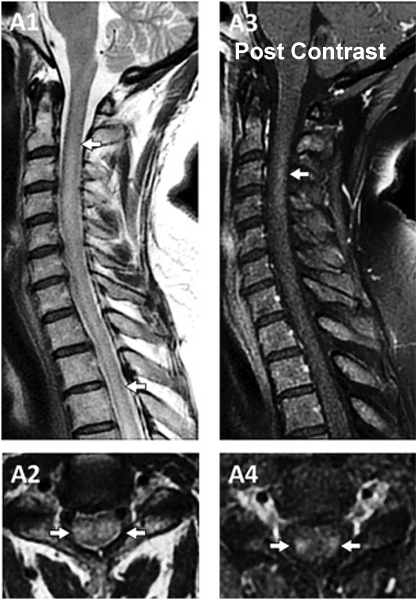

Q7: A 75-year-old woman with history of prior cervical spine decompression presented with progressive neck pain, asymmetric hand tingling, and neuropathic pain, followed by urinary incontinence and gait difficulty. Sagittal T2 weighted imaging likely shows?.